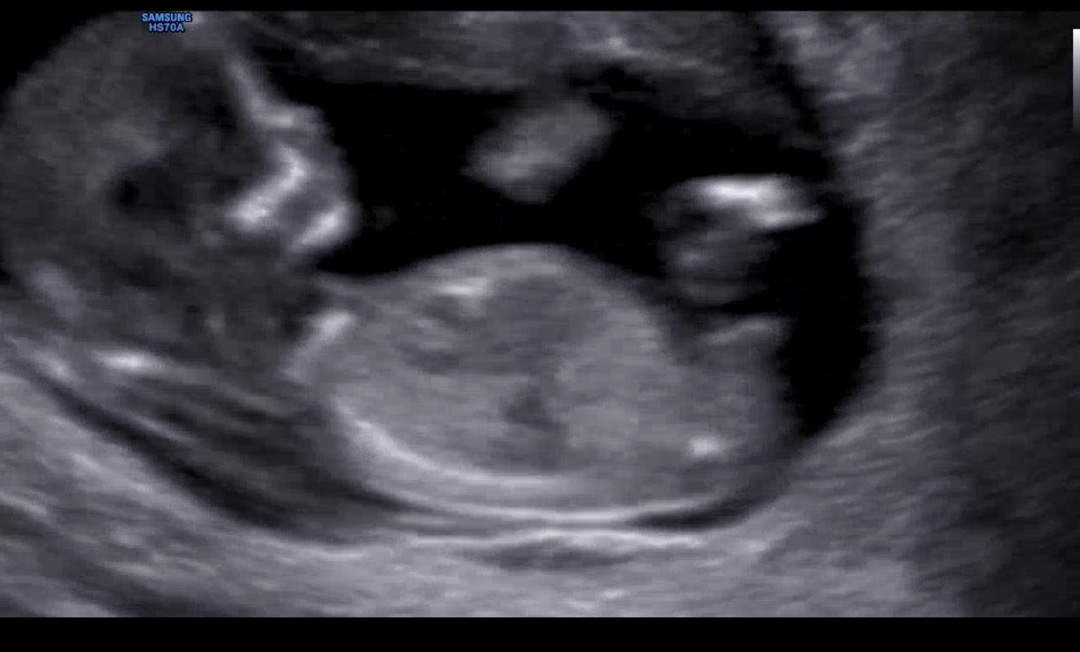

각도법 아들 딸? 궁금해요 고수님들

12주2일이에요!